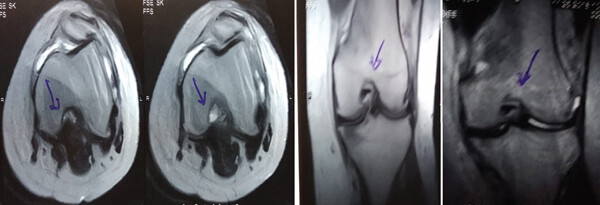

MRI:治療前后的MRI結(jié)果

治療前 MRI 顯示內(nèi)側(cè)和外側(cè)半月板后角 III 級撕裂。

治療后MRI檢查顯示內(nèi)側(cè)和外側(cè)半月板后角撕裂有所改善。患者癥狀改善,日常生活活動能力增強。

結(jié)論:間充質(zhì)干細胞治療后,MRI檢查顯示內(nèi)側(cè)和外側(cè)半月板后角撕裂有所改善 ,關(guān)節(jié)功能也有改善,未出現(xiàn)嚴(yán)重不良事件。可以達到干細胞治療半月板損傷短期療效的目標(biāo)。